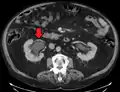

- Stone causing hydronephrosis[14]